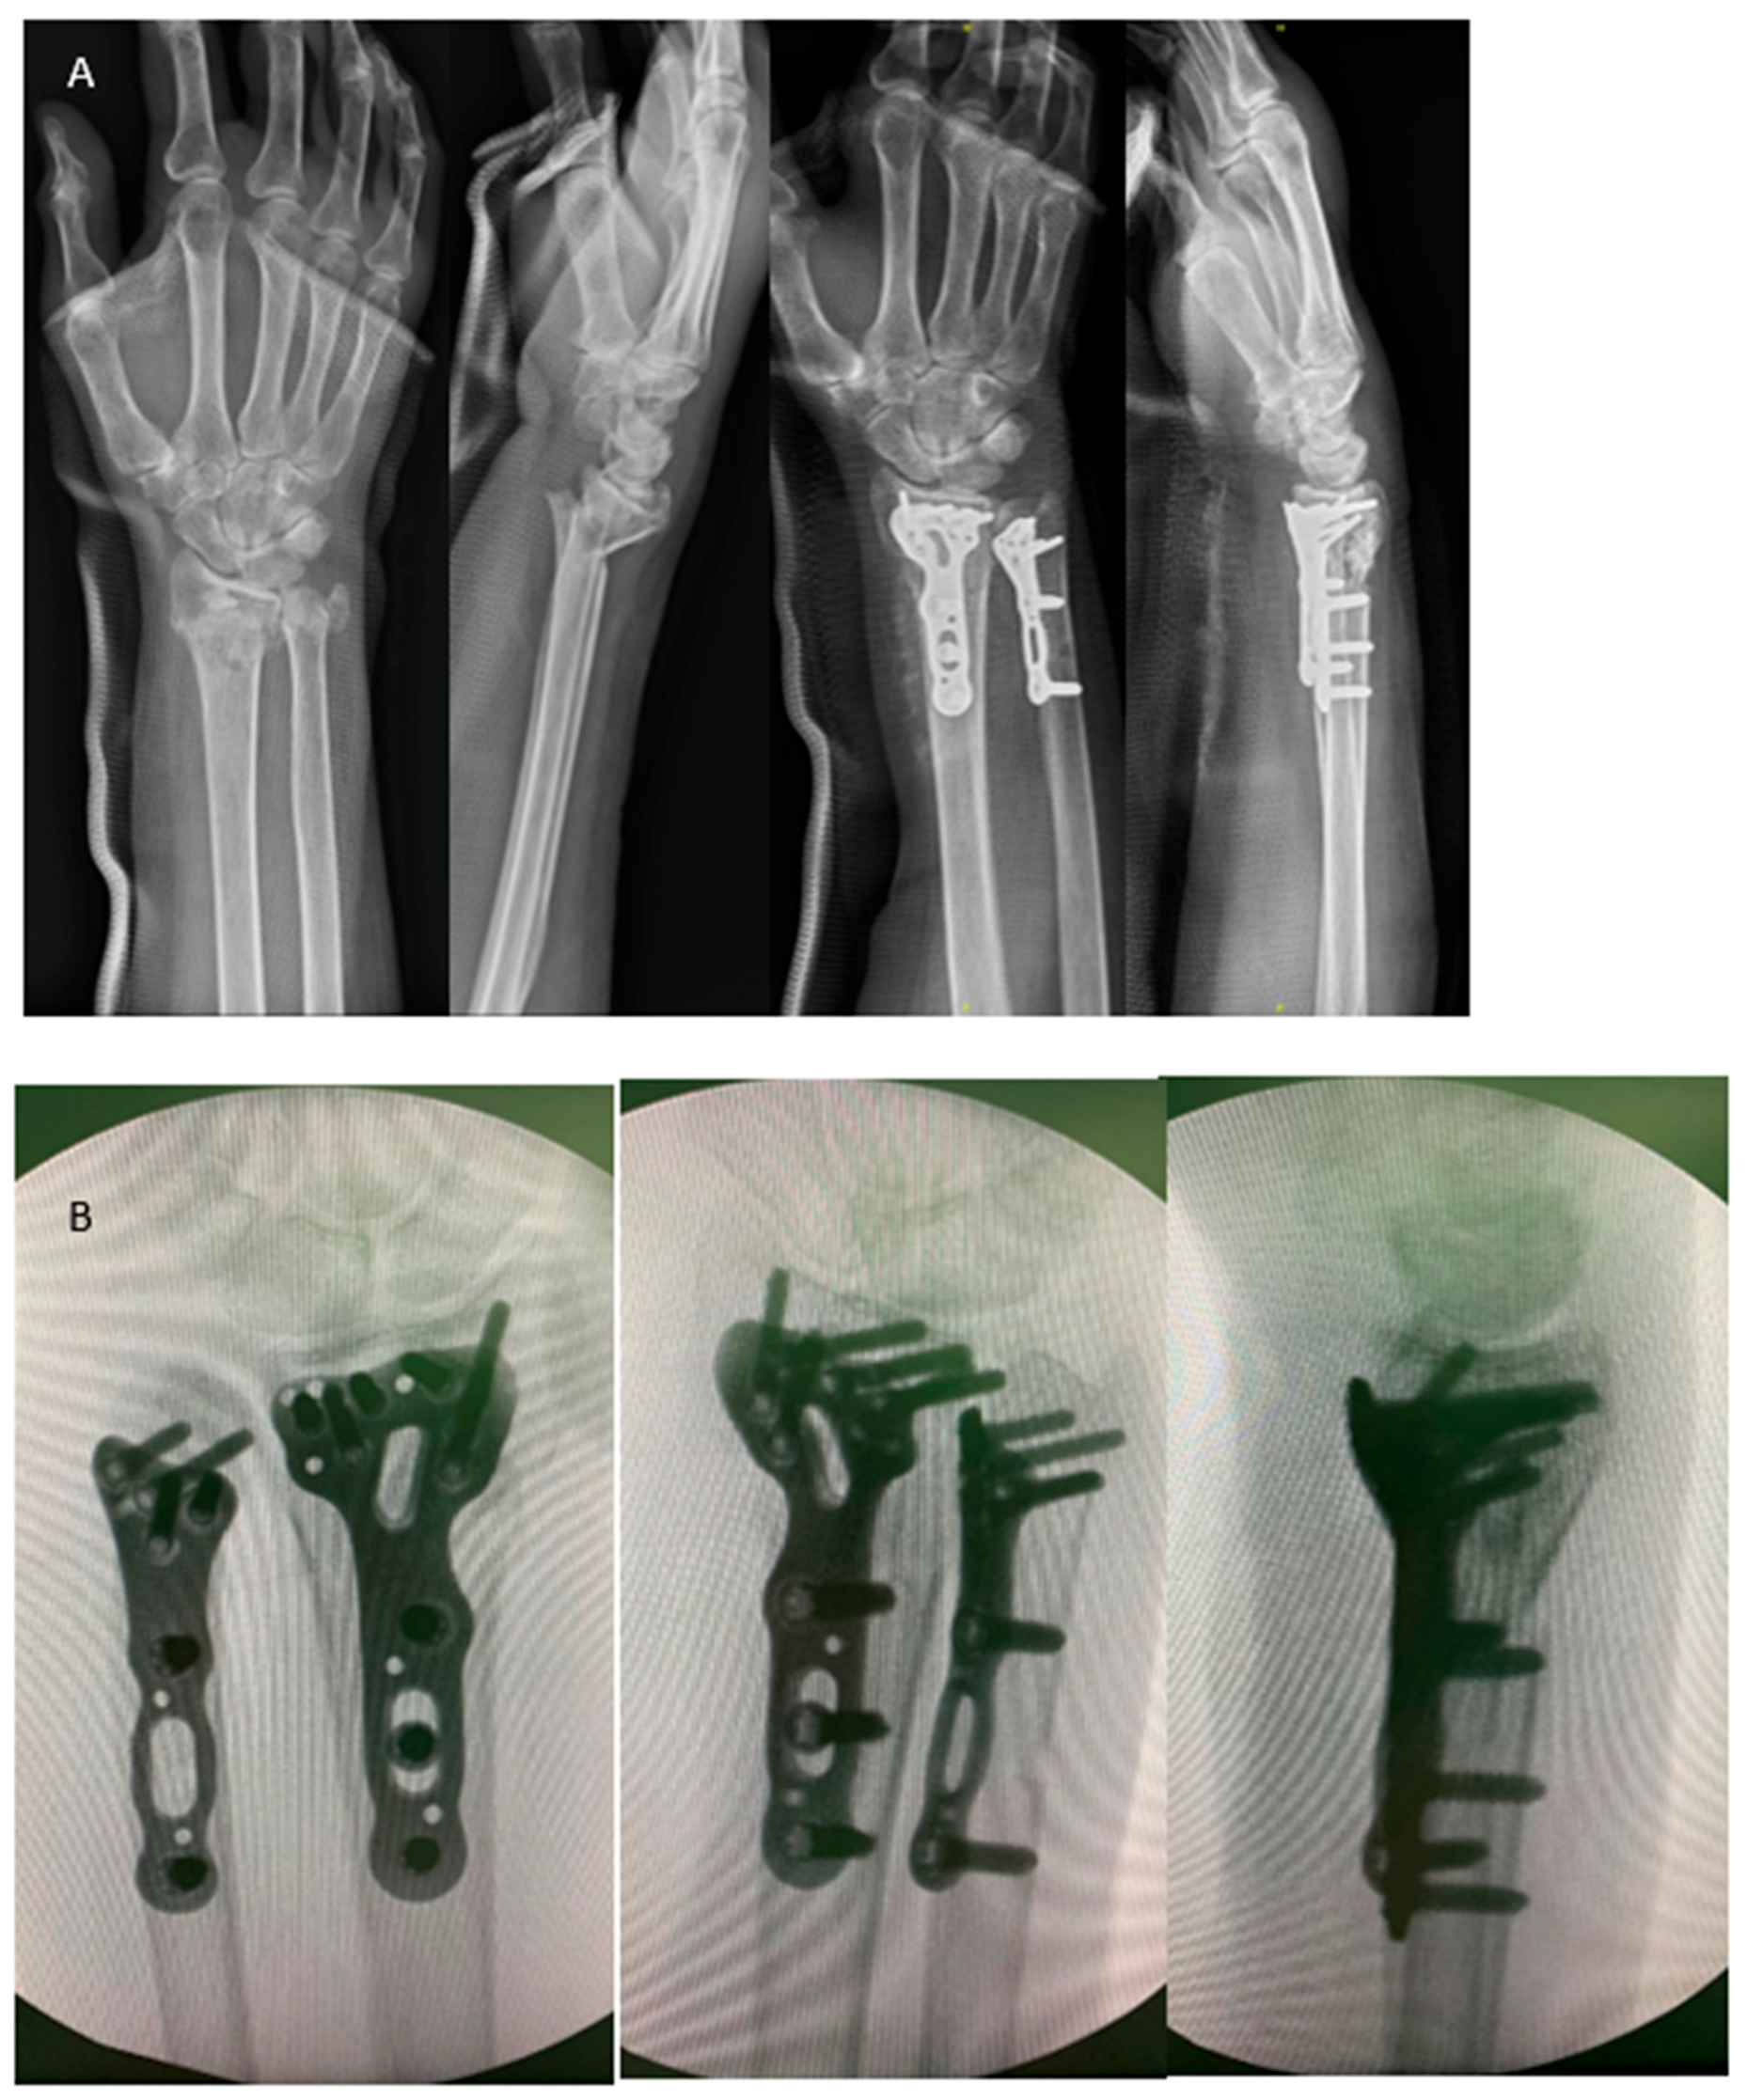

At the last follow-up, wrist flexion was 67 ± 11° and extension was 69 ± 13°. Forearm pronation was 81 ± 9° and supination was 79 ± 15°. Grip strength was 28.3 ± 11.5 kg, which was 88% of the uninjured opposite side. The mean Quick DASH score was 13.9 ± 11.5. The mean VAS during activity was 0.5 ± 0.9. The postoperative radiographic parameters were as follows: radial height: 10.8 ± 1.7 mm, radial inclination: 22.6 ± 3.7°, volar tilting: 4.0 ± 3.9°, and ulnar variance: −0.4 ± 1.4 mm. There were no cases of infection, neurovascular injury, or malreduction among these patients. However, impingement on the sigmoid notch of the radius caused by the ulnar implant, necessitating implant removal, was reported in two patients (15.4%) (Figure 4). Clinical results and radiographic parameters are summarized in Table 2.

Figure 4.

The figure shows a right distal forearm comminuted fracture pre- and post-operatively at nine months. The ulna implant was removed due to irritation, which caused bony erosion at the DRUJ. The white arrow indicates the erosion near the sigmoid notch.